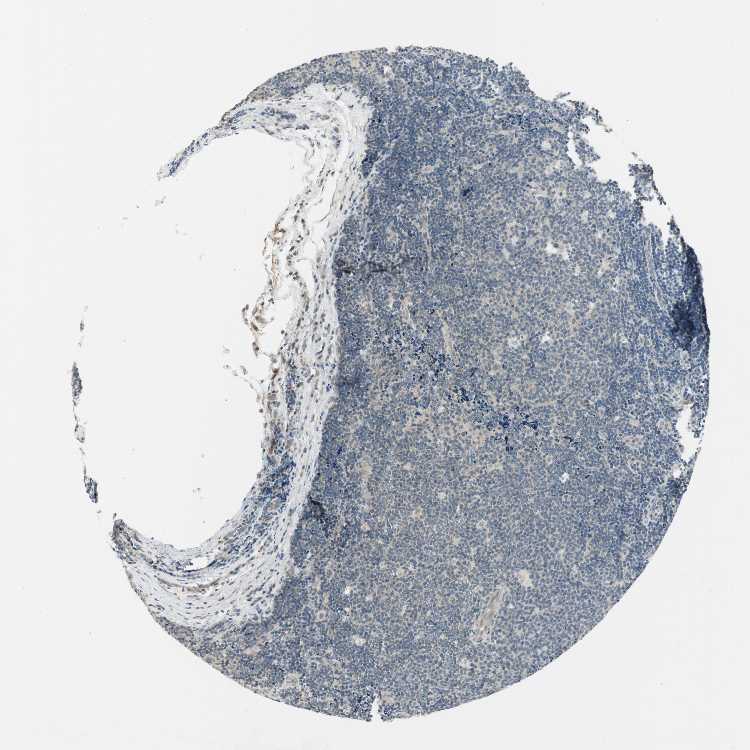

LYMPH NODE - Antibody stainingi

Antibody staining in the annotated cell types in the current human tissue is reported as not detected, low, medium, or high, based on conventional immunohistochemistry profiling in selected tissues. This score is based on the combination of the staining intensity and fraction of stained cells.

Each image is clickable and will lead to virtual microscopy that enables deeper exploration of all samples and also displays staining intensity scores, fraction scores and subcellular localization as well as patient and tissue information for each sample.

Antibody HPA007172Antibody CAB026471

Germinal center cells LowMedium

Non-germinal center cells Not detectedMedium